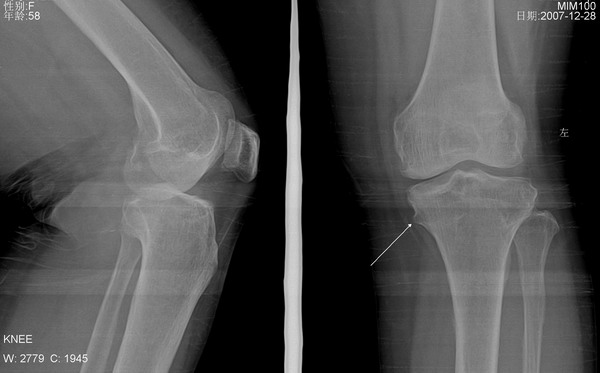

左侧膝关节疼痛

1、左膝关节退行性骨关节病伴关节积液。

2、胫骨干骺端骨软骨瘤。

左侧胫骨上干骺端内侧骨软骨瘤。

支持左侧胫骨近侧干骺端内侧骨软骨瘤。

1、左膝关节退行性骨关节病。

支持骨软骨瘤,关节积液看不出来。另有骨质增生。

左侧胫骨近侧干骺端内侧骨软骨瘤,左膝关节退行性骨关节病